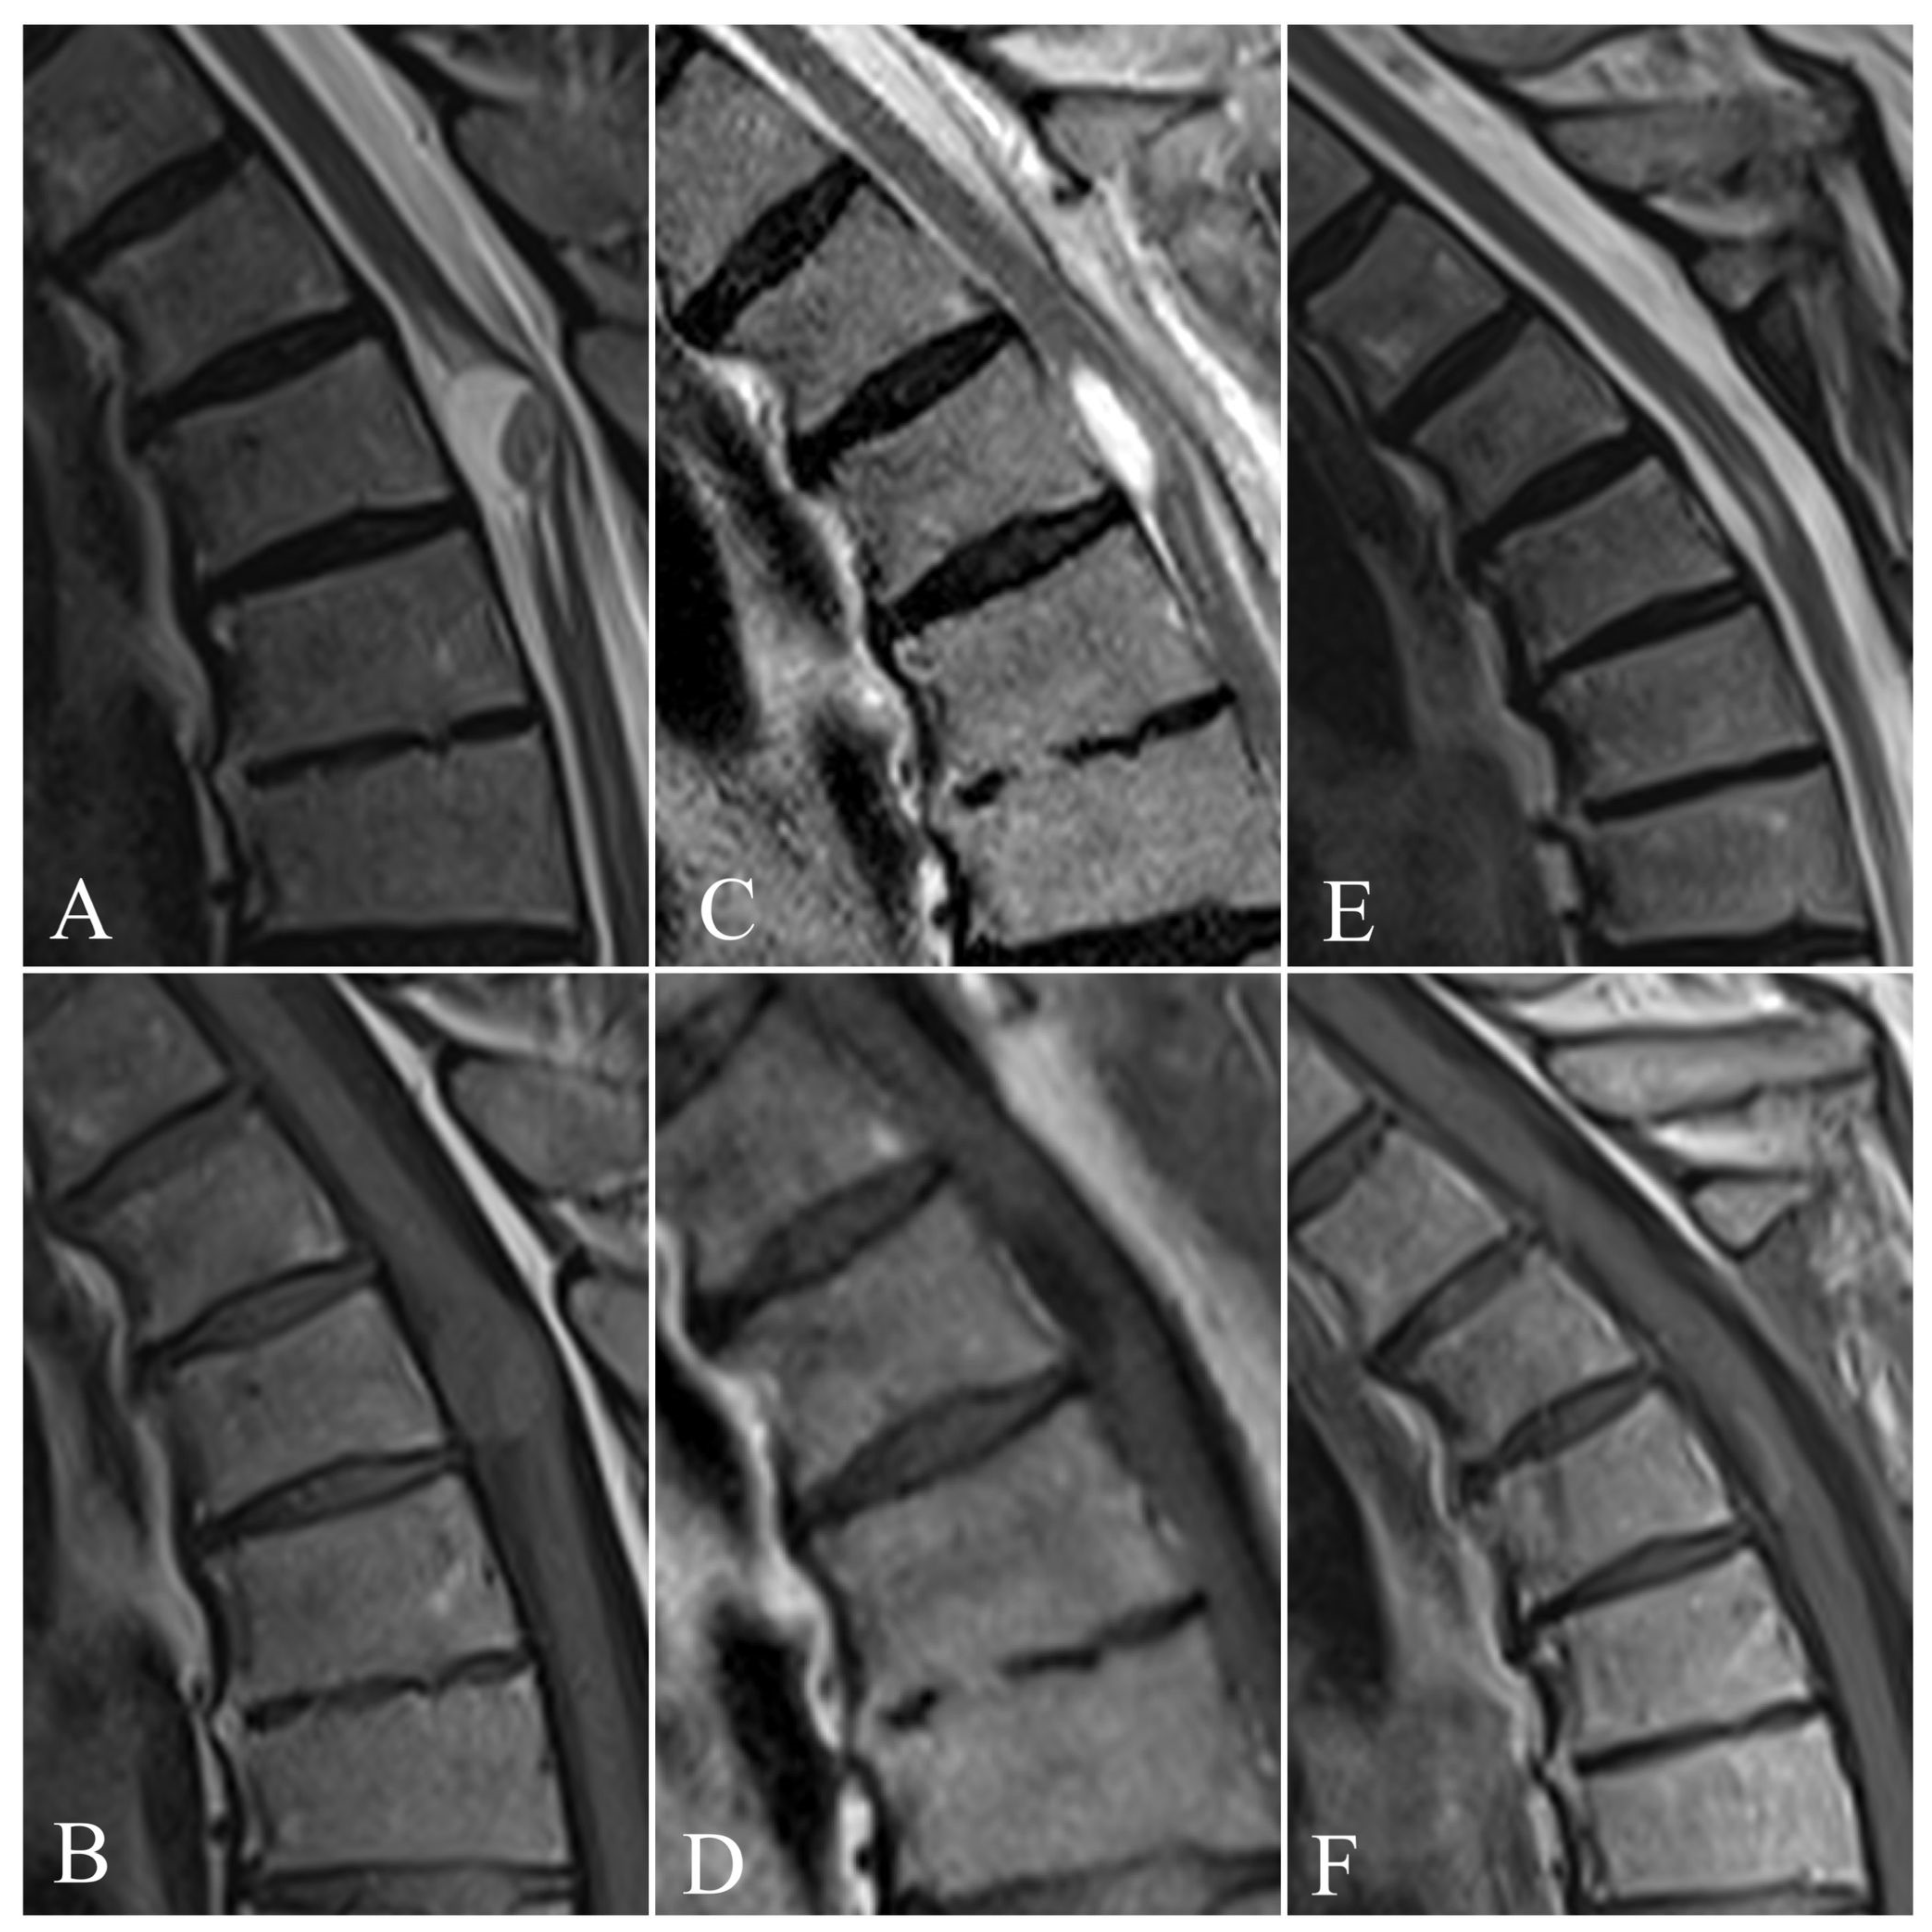

4.4. Neuroimaging Features